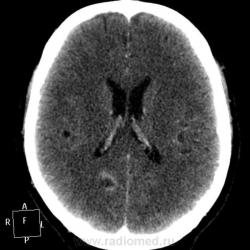

Мужчине 67 лет. У меня нет четкого мнения об изменении в правой затылочной доле. Ваше мнение?

"Непонятная штука в затылочной доле"-вероятнее артерио-венозная мальформация.Гиподенсная зона,прилежащая к ней-отдаленное последствие кровоизлиния из АВМ.

Может кавернома.

Склоняюсь к АВМ, прослеживается приводящий и отводящий сосуды. Не совсем понятно понижение плотности между сосудистыми петлями (может, коллега gar70 прав/а). Рекомендовала МРТ после выписки из сосудистого отделения (у нас такие вещи, что бы из сосудистых аномалий ни было, не оперируют).